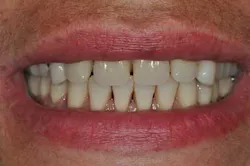

Fig. 2: Anterior teeth relationships prior to treatment

The patient’s main problem is adult aggressive periodontitis, aggravated by tobacco use. The consequent tooth losses have caused migrations of the remaining teeth under functional adaptation.